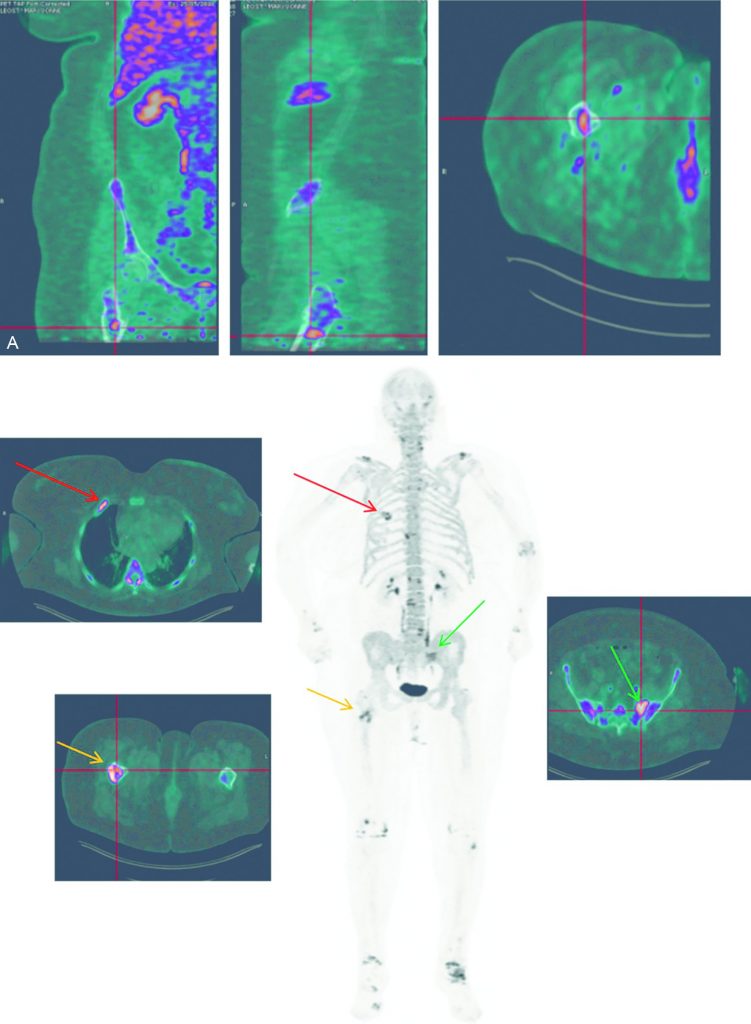

Fig. 34.6 TEP-TDM au 18FNa pour une patiente suspecte de récidive de cancer du sein.

A. Petite lésion osseuse fémorale droite isolée. B. Mise en évidence de localisations secondaires osseuses costale droite (flèche rouge), du sacrum latéralisé à gauche (flèche verte) et de la diaphyse fémorale droite (flèche orange). À noter une atteinte arthrosique diffuse (rachis, acromion, genoux et chevilles).

Source : CERF, CNEBMN, 2022.